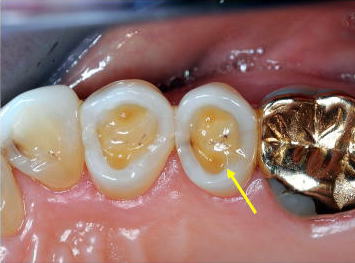

■症例1−3 酸蝕症 Acid Erosion

前歯切端と臼歯部咬合面に診られる広範囲のEnamel質欠損